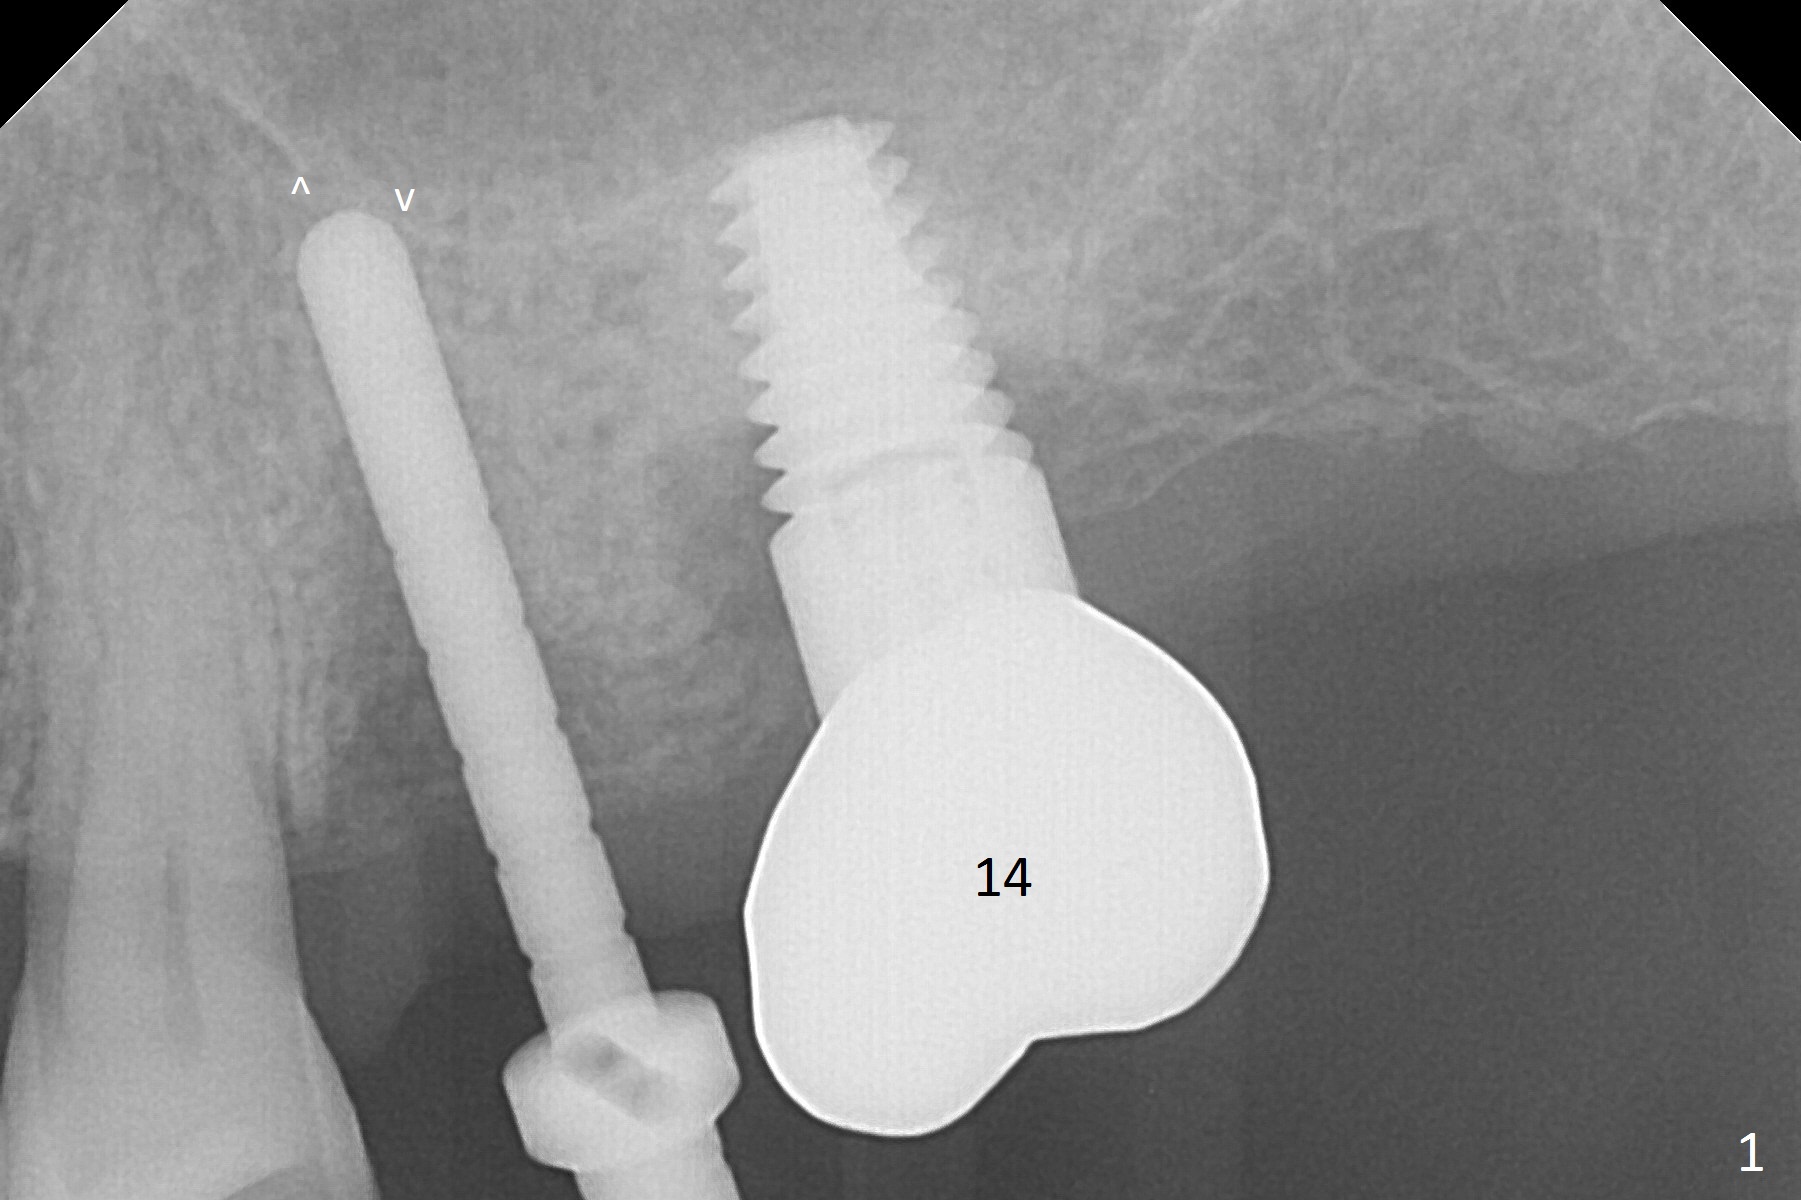

Although there is buccal atrophy at #14 (Fig.4 *), no bone graft is going to be done since it is asymptomatic. It appears that the implant is too large for the site.

A parallel pin is not able to be inserted as deep as a 2 mm drill at #13 (Fig.1); at that time perforation of the sinus floor is not detected (arrowheads).

A Linderman bur is used to move the initial osteotomy distal. By the time of 3 mm in place, the trajectory seems to have improved; the sinus floor has been penetrated (Fig.2). Retrospectively, the parallel pin is not as sharp as the 2 mm drill to penetrate the perforated sinus floor (Fig.1).